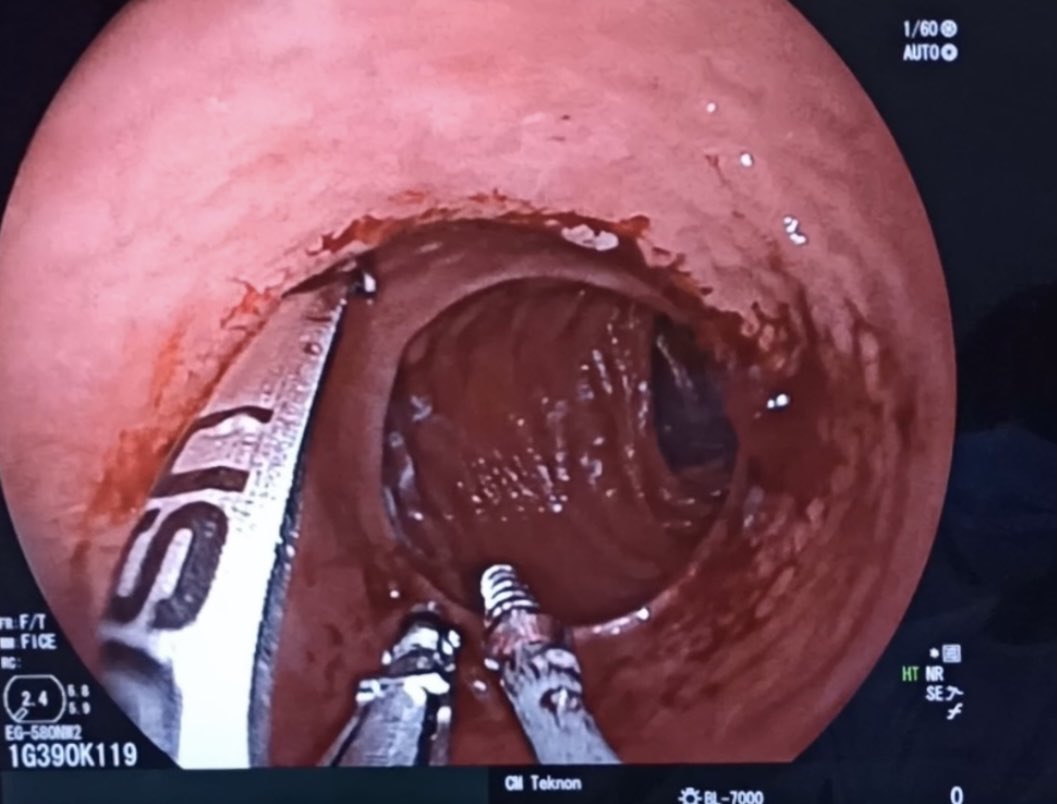

#MedCase 🧓 65 años con ingesta accidental de cuerpo extraño hace 24 horas. Intento fallido de extracción es referida para tratamiento. Endoscopia asistida por cap. Retiro con campaña “artesanal” de Hood. Se observa laceración esofágica y colocación de clips.

Sequence of first bite for a #Rose procedure for reparation of #bypass #RNY of 5 cm pouch with an anastomosis over 25 mm. We used the 33 mm @USGIMedical #Gprox avoiding the #APC due the lack of space #bariatricendoscopy @sa6ater @MetabolicEndo @SighPichamol thoughts?

2nd and 3rd bites. Less than 10 minutes procedure. Safe, clean and effective. @Clinica_Teknon #bariatricendoscopy #bypassreparation #ROSEprocedure #obesidad #endoscopia @EEndoscopia @TerapiasObesid